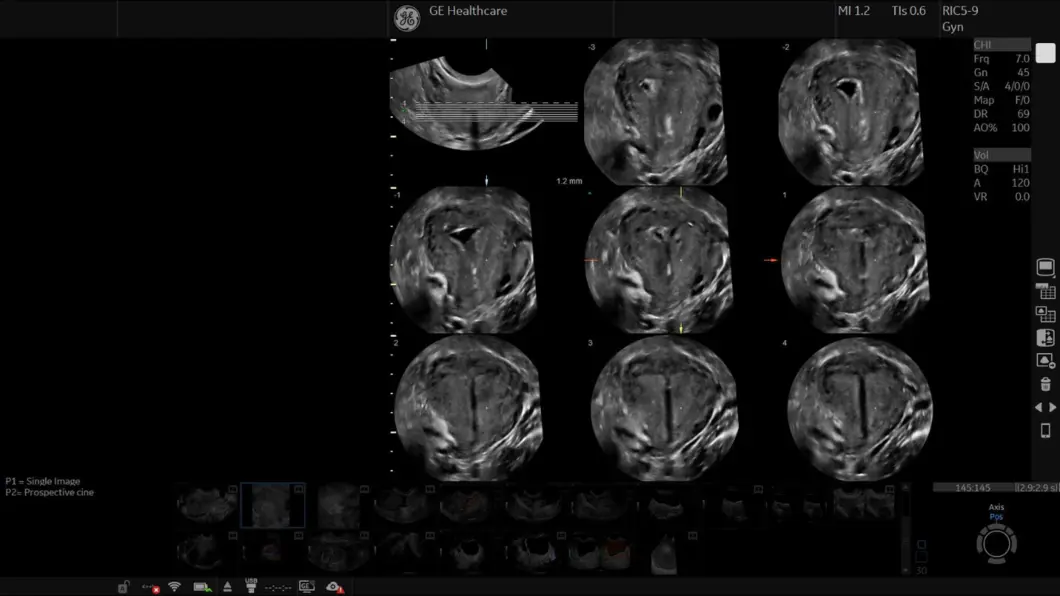

LOGIQ Fortis je vaše ultrazvučno rješenje za svakog pacijenta – od glave do pete, od pretile do mršave osobe, od novorođenčadi do gerijatrijske dobi, za sve u vašoj ustanovi. Skenirajte pomoću baterijskog napajanja za provođenje ispita bilo gdje.

Opremljen tehnologijom snimanja sljedeće generacije, LOGIQ Fortis je vaše pristupačno sveobuhvatno ultrazvučno rješenje za snimanje cijelog tijela.

Naša moćna cSound™ arhitektura povećava snagu obrade i protok podataka kombiniranjem XDclear™ sondi i cSound Imageformer-a s naprednom tehnologijom Speckle Reduction Imaging (SRI). Rezultat je iznimna kvaliteta slike, jasnoća i klinička pouzdanost u širokom rasponu kliničkih primjena.